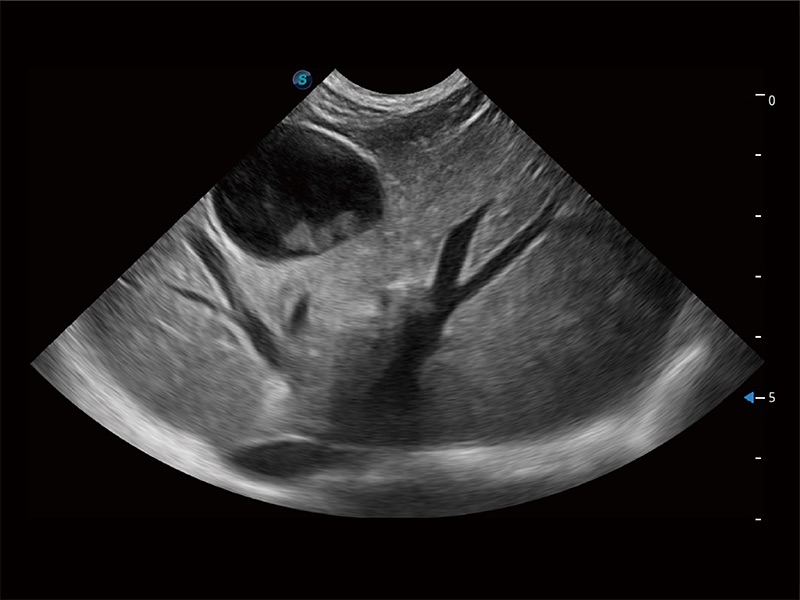

高性能和先進(jìn)的臨床應(yīng)用工具可以為動(dòng)物醫(yī)生提供臨床信心。ProPet 80 搭載了先進(jìn)的腹部和淺表應(yīng)用工具,幫助醫(yī)生在日常臨床實(shí)踐中發(fā)揮前所未有的作用。

非線性融合造影成像充分利用諧波和基波信號(hào),為難以觀察的血流進(jìn)行增強(qiáng)顯像??捎糜诰€陣、凸陣、微凸陣、相控陣探頭。